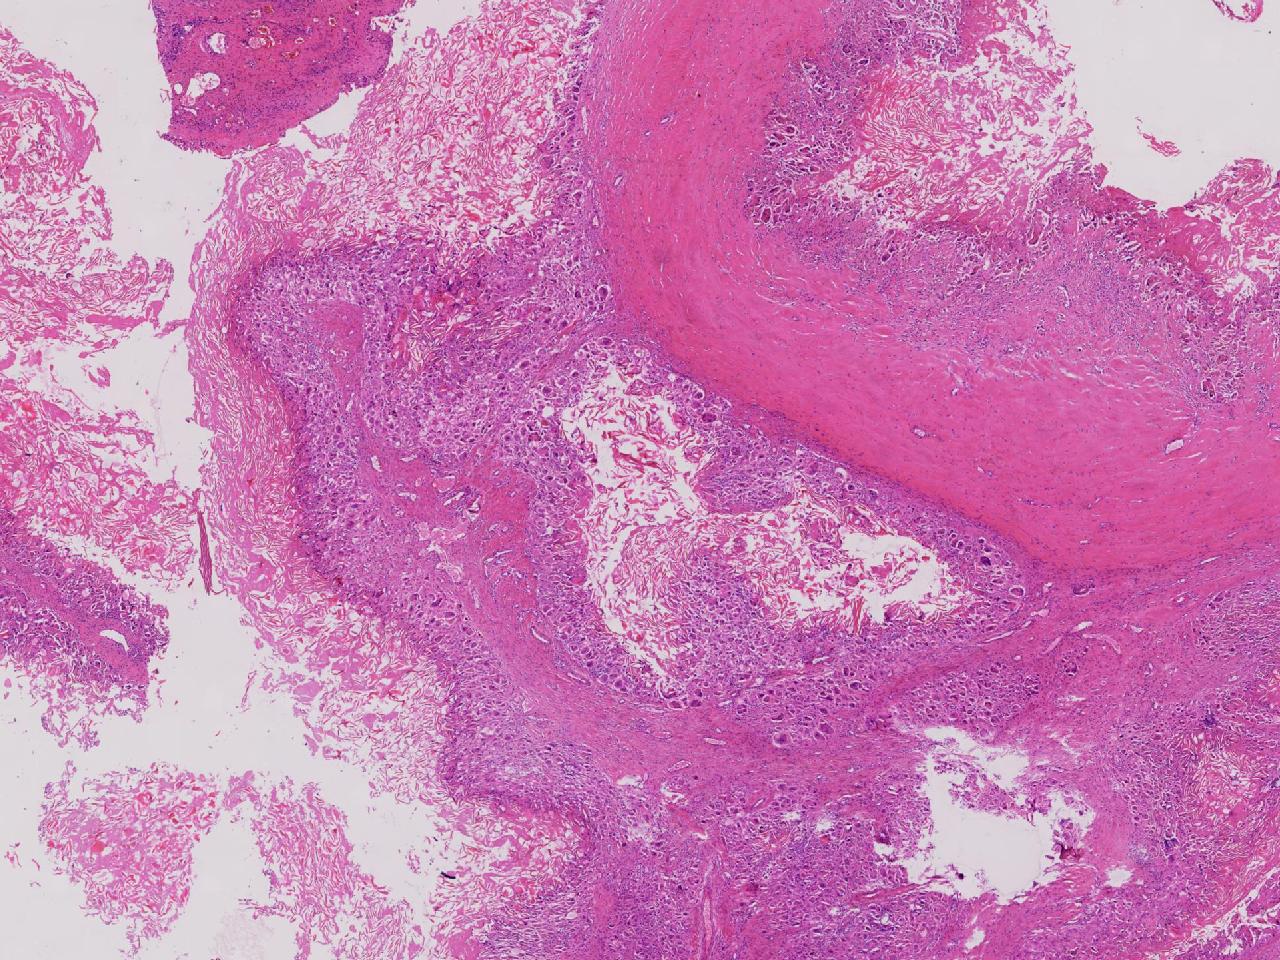

皮样/表皮样囊肿伴周边异物巨细胞反应?

右侧臀部皮下肿物10余年,渐增大,无破溃,无疼痛。

右侧臀部皮下肿物

囊性肿物一个,直径2.5厘米,肿物位于皮下。

异物肉芽肿性炎?

表皮样囊肿伴异物肉芽肿性炎。